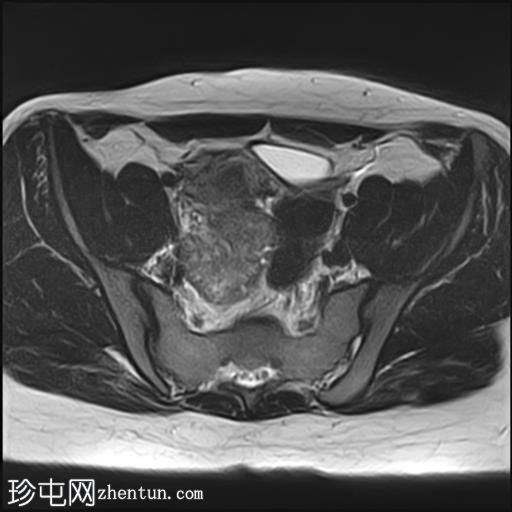

轴位

T2加权像

盆腔内可见多个边界清晰的肿块:

其中一个位于子宫上方,T2加权像呈中等信号,中心区域呈高信号,增强T1脂肪抑制像未见强化。右侧卵巢增大,增厚的血管蒂扭曲,未见强化,轴位和矢状位T2加权像均显示清晰。

另一个位于子宫后窝,T2加权像呈中等信号,增强扫描显示明显强化。

轻度腹腔积液